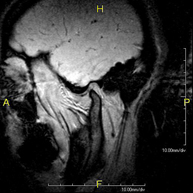

Prova diagnòstica no invasiva que consisteix en l'obtenció d'imatges d'alta definició anatòmica del cerbell mitjançant l'ús d'un camp electromagnètic i ones de ràdio (com un emissor i un receptor). No utilitza radiació ionitzant. Indicacions: problemes vasculars, pèrdua de memòria, epilèpsia, cefalea, malformacions, sospita de tumor, meningitis. - RM de Cais

- RM Cerebral (cranial)